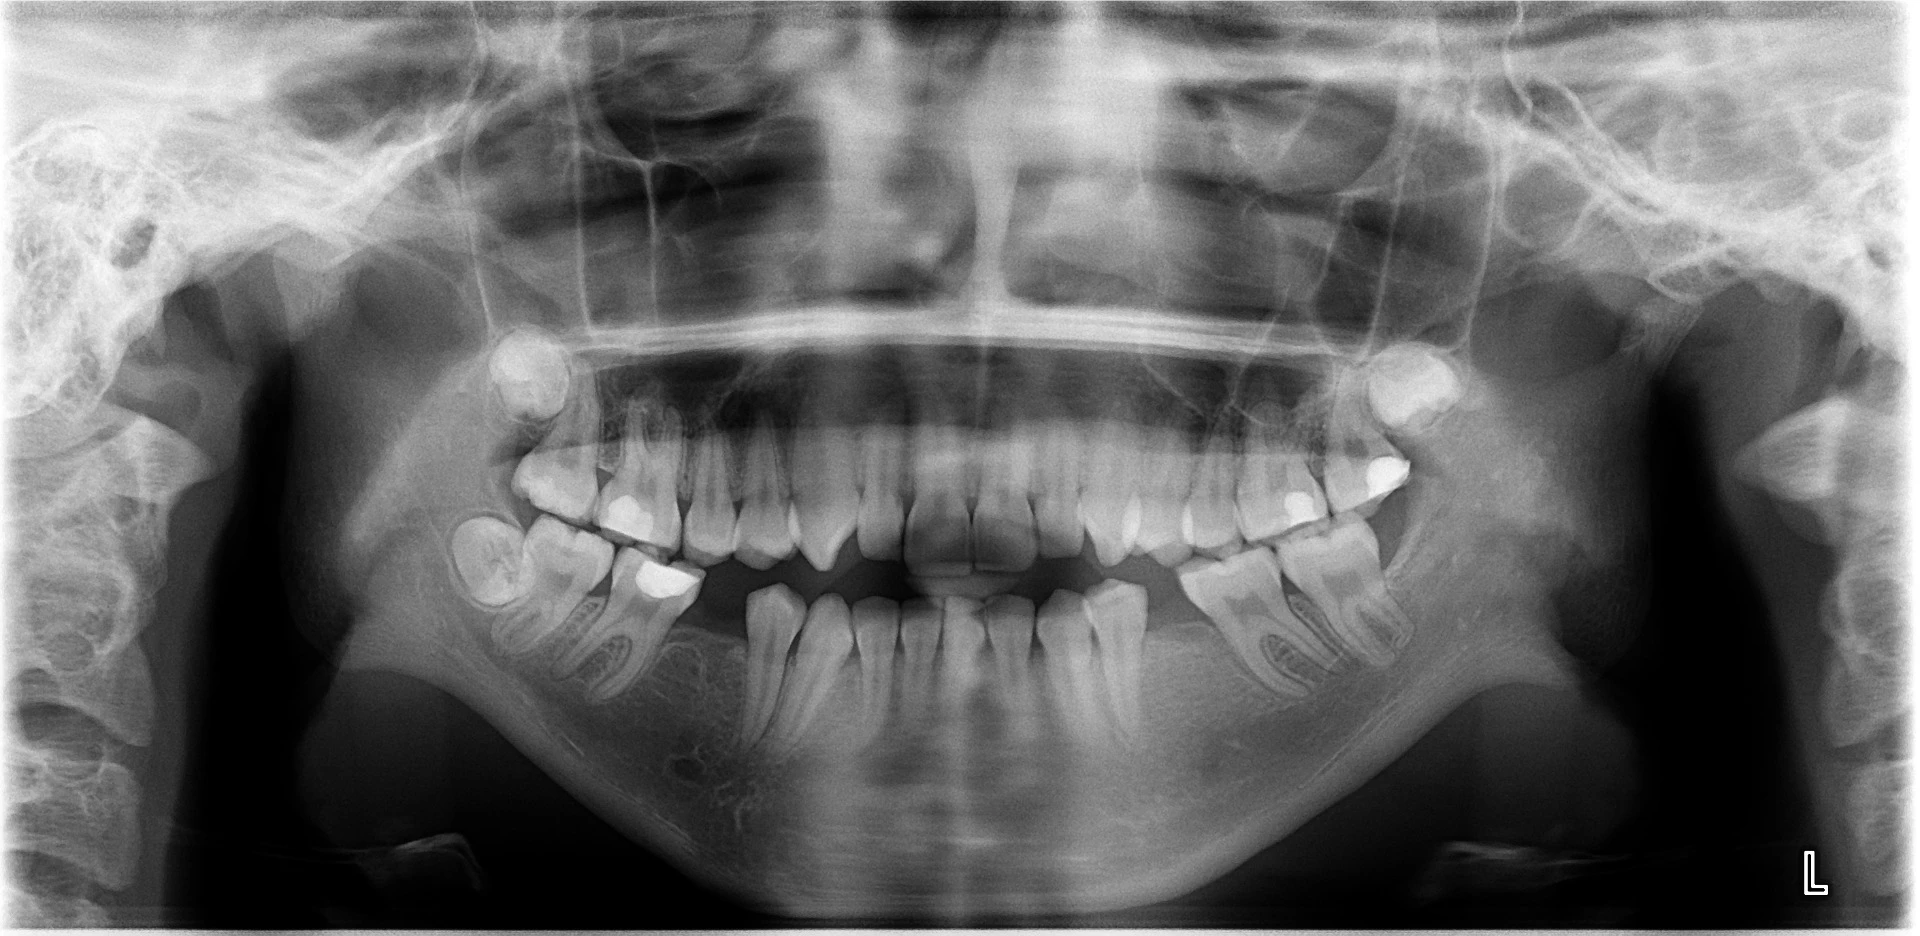

Vårt arbeid

Alle pasienter som vises har gitt skriftlig samtykke til at bildene kan brukes på klinikkens nettside.